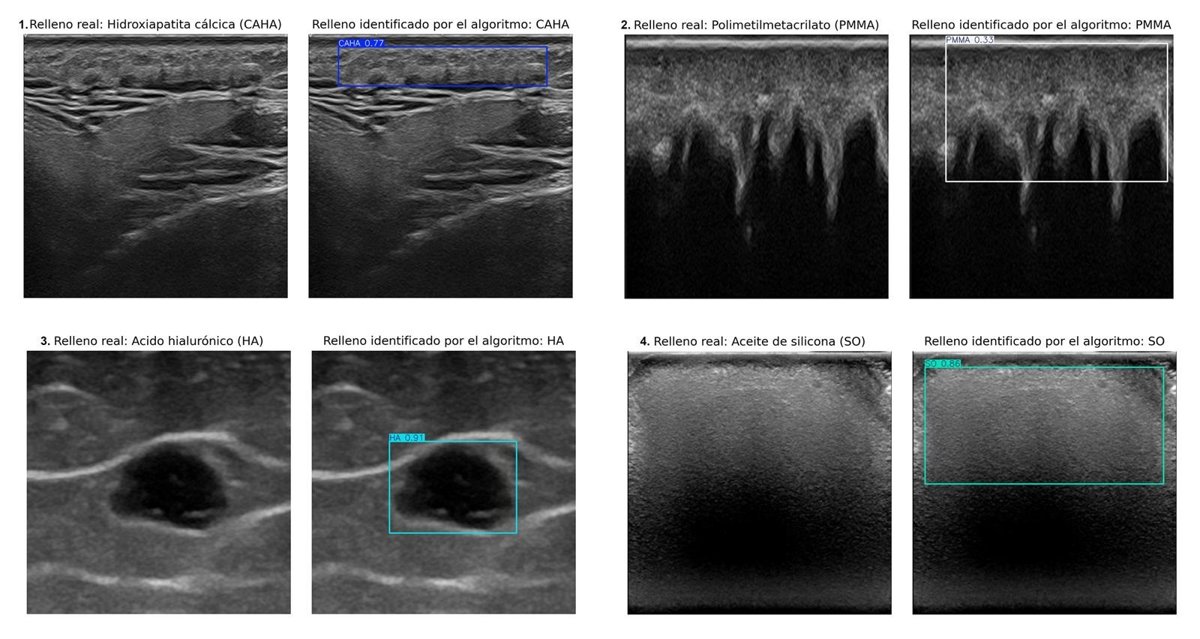

Ecografías que muestran rellenos estéticos identificados por un especialista (izquierda) y las regiones detectadas por el algoritmo (derecha). En los cuatro casos, el algoritmo acertó en clasificar y delimitar el área de cada relleno.

Ecografías que muestran rellenos estéticos identificados por un especialista (izquierda) y las regiones detectadas por el algoritmo (derecha). En los cuatro casos, el algoritmo acertó en clasificar y delimitar el área de cada relleno. - UGR

Este algoritmo es capaz de identificar y discriminar automáticamente, en imágenes ecográficas, cuatro tipos de rellenos cosméticos: hidroxiapatita cálcica, ácido hialurónico, polimetilmetacrilato y aceite de silicona.